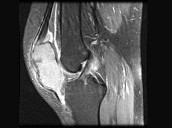

- 单项选择题女,30岁, 膝痛四月余,结合图像, 最可能的诊断是 ( )

A、畸形性骨炎

B、嗜酸肉芽肿

C、成软骨细胞瘤

D、骨囊肿

E、骨巨细胞瘤